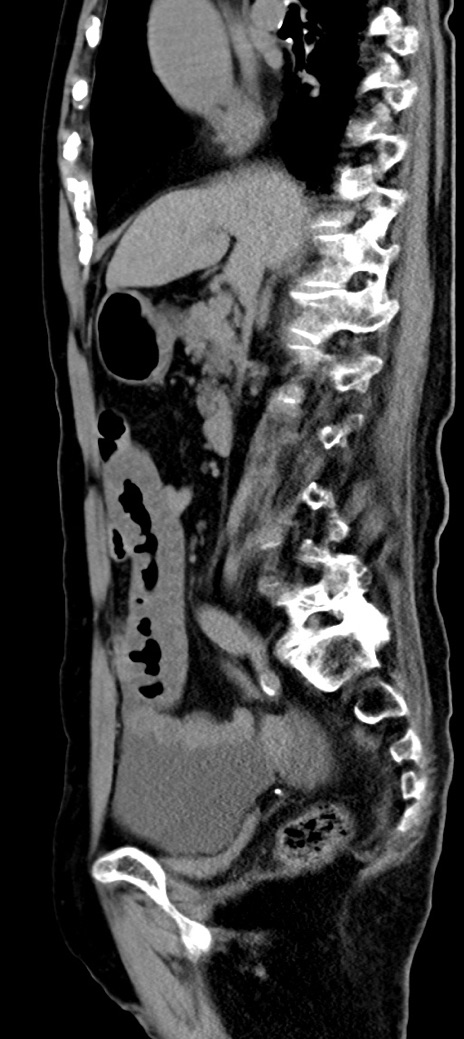

症例40(矢状断像)他院1日前

【症例】90歳代女性

【主訴】腹痛・嘔吐

【現病歴】 食欲低下、嘔吐があり昨日他院受診。肺炎と診断され入院となる。入院後より腹部全体に圧痛あり。胃管留置され経過みていたが、症状持続するため、

当院転院となる。

【既往歴】胸椎圧迫骨折、胆石症

【身体所見】腹部:中央に激痛あり、圧痛あり、反跳痛不明

【データ】WBC 17100、CRP 18.82